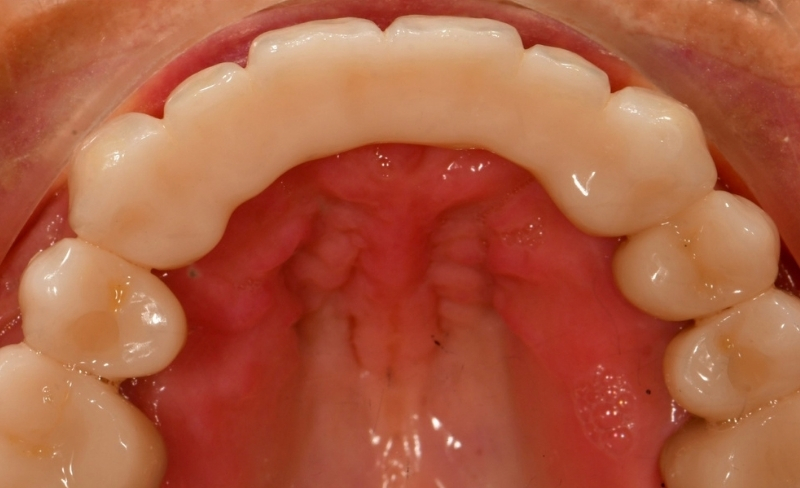

Smile makeover to manage the failing upper bridge using crowns, bridges and dental implants.